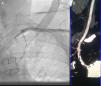

We performed the angioplasty of the SCA via a retrograde access from the left radial artery. The crossing of the lesion was laborious; we used many wires and even coronary wires (Whisper MS, Pilot 150 and Miracle 4) (Figure 3). Finally, a TIF Tip™ 0.018 Terumo Hydrophilic Guidewire was advanced through the catheter and the SCA occlusion was barely crossed, using a retrograde subintimal dissection. Predilation using a coaxial balloon (Admiral Xtreme, Medtronic, 4×40 mm) was performed to the nominal diameter after confirming the intravascular position (Figure 3). Next, a balloon expandable stent (6×37 mm) was inserted without complications. A final proximal optimizing post-stenting angioplasty was performed. The final angiography showed a good result with TIMI III flow in the LIMA (Figure 3). Immediately after the procedure, the patient had a normal radial pulse. Six months later, his LVEF had improved (LVEF=45%).

(a) First we crossed the lesion in a false lumen with a stiff guidewire with retrograde dissection of the aorta, so we withdrew the guidewire; (b) Attempt to cross the lesion with a coronary guidewire (Miracle 6); (c) Predilation of the lesion after the positioning of a TIF Tip™ 0.018 Terumo Hydrophilic Guidewire in subintima; (d) Release of the stent at the stenosis of the subclavian artery with 1 cm into the aorta; (e) Postdilation of the stent; (f) Final result with no residual stenosis and TIMI III flow of left internal mammary artery.